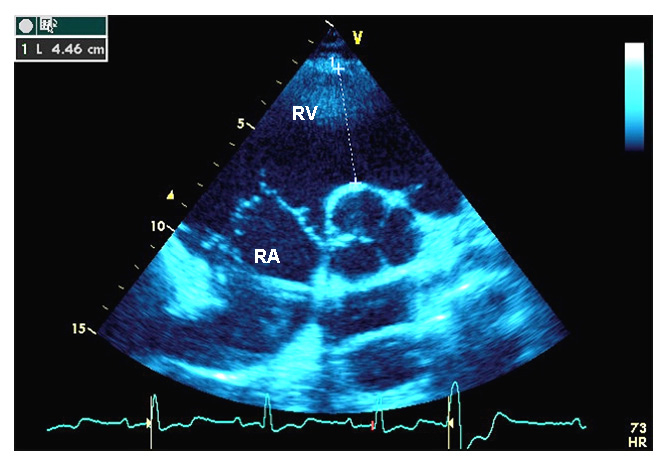

At the age of thirteen, the clinical examination was consistent with curly and woolly blond hair with high frontal hairline. Although shape and dental enamel of teeth were normal, she had dental agenesis with missing teeth numbers 14, 15, 17, 25, 27, 35, 37, 45 and 47. Furthermore she exhibited slight plantar keratosis, toe intertrigo and minimal palmar keratosis. Nail examination revealed bilateral leuconychia of third and fourth toe whereas finger nails were normal. While she had no cardiac symptoms, her resting electrocardiogram showed regular sinus rhythm, left hemi bundle-branch block and an epsilon wave. Her Holter ECG recordings showed frequent ventricular premature beats. Echocardiographic findings were consistent with severe RV dilatation and slight LV enlargement from the apical-4 chamber view (fig. 2A, B). At 22 years, an ICD was implanted following three episodes of syncope.

Figure 2

Transthoracic echocardiography, and genetic screening of case 2.

A  Parasternal short axis view. Right atrium and right ventricular infundibulum are indicated. The right ventricular infundibulum diameter is measured at the level of the aortic valve.

RA = right atrium; RV = right ventricular infundibulum.